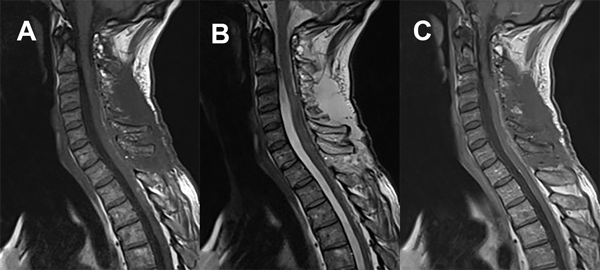

Se comprueba el grado de resección tumoral con RM de columna cervical confirmando la exéresis total macroscópica. Además, se realiza TC de columna cervical de control (Figuras 8 y 9).

Figura 8. RM de columna cervical. A) Secuencia T1. Corte sagital. B) Secuencia T2. Corte sagital. C) Secuencia T1 con contraste. Corte sagital.